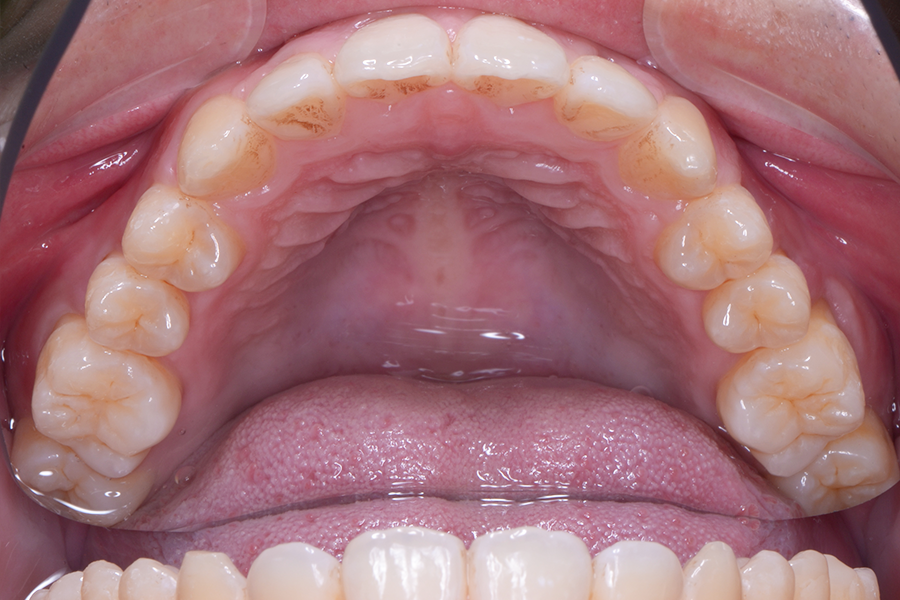

• 治療前